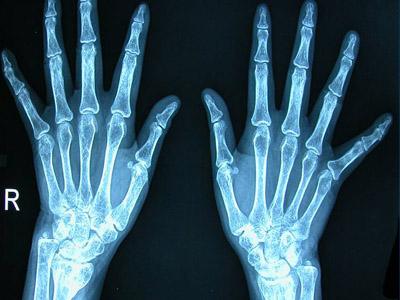

类风湿关节炎(RA)是一种病因未明的慢性、以炎性滑膜炎为主的系统性疾病。其特征是手、足小关节的多关节、对称性、侵袭性关节炎症,经常伴有关节外器官受累及血清类风湿因子阳性,可以导致关节畸形及功能丧失。